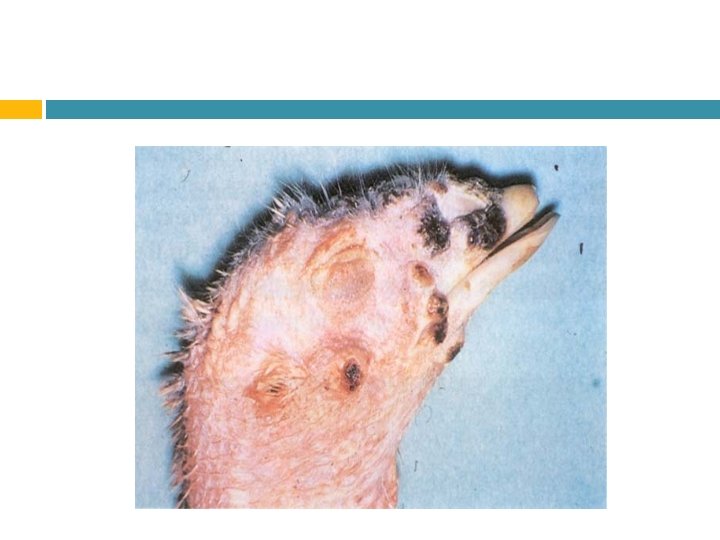

Síntomas Produce : Decaimiento Plumas erizadas Alas caidas Diarrea Cianosis Cabeza negra